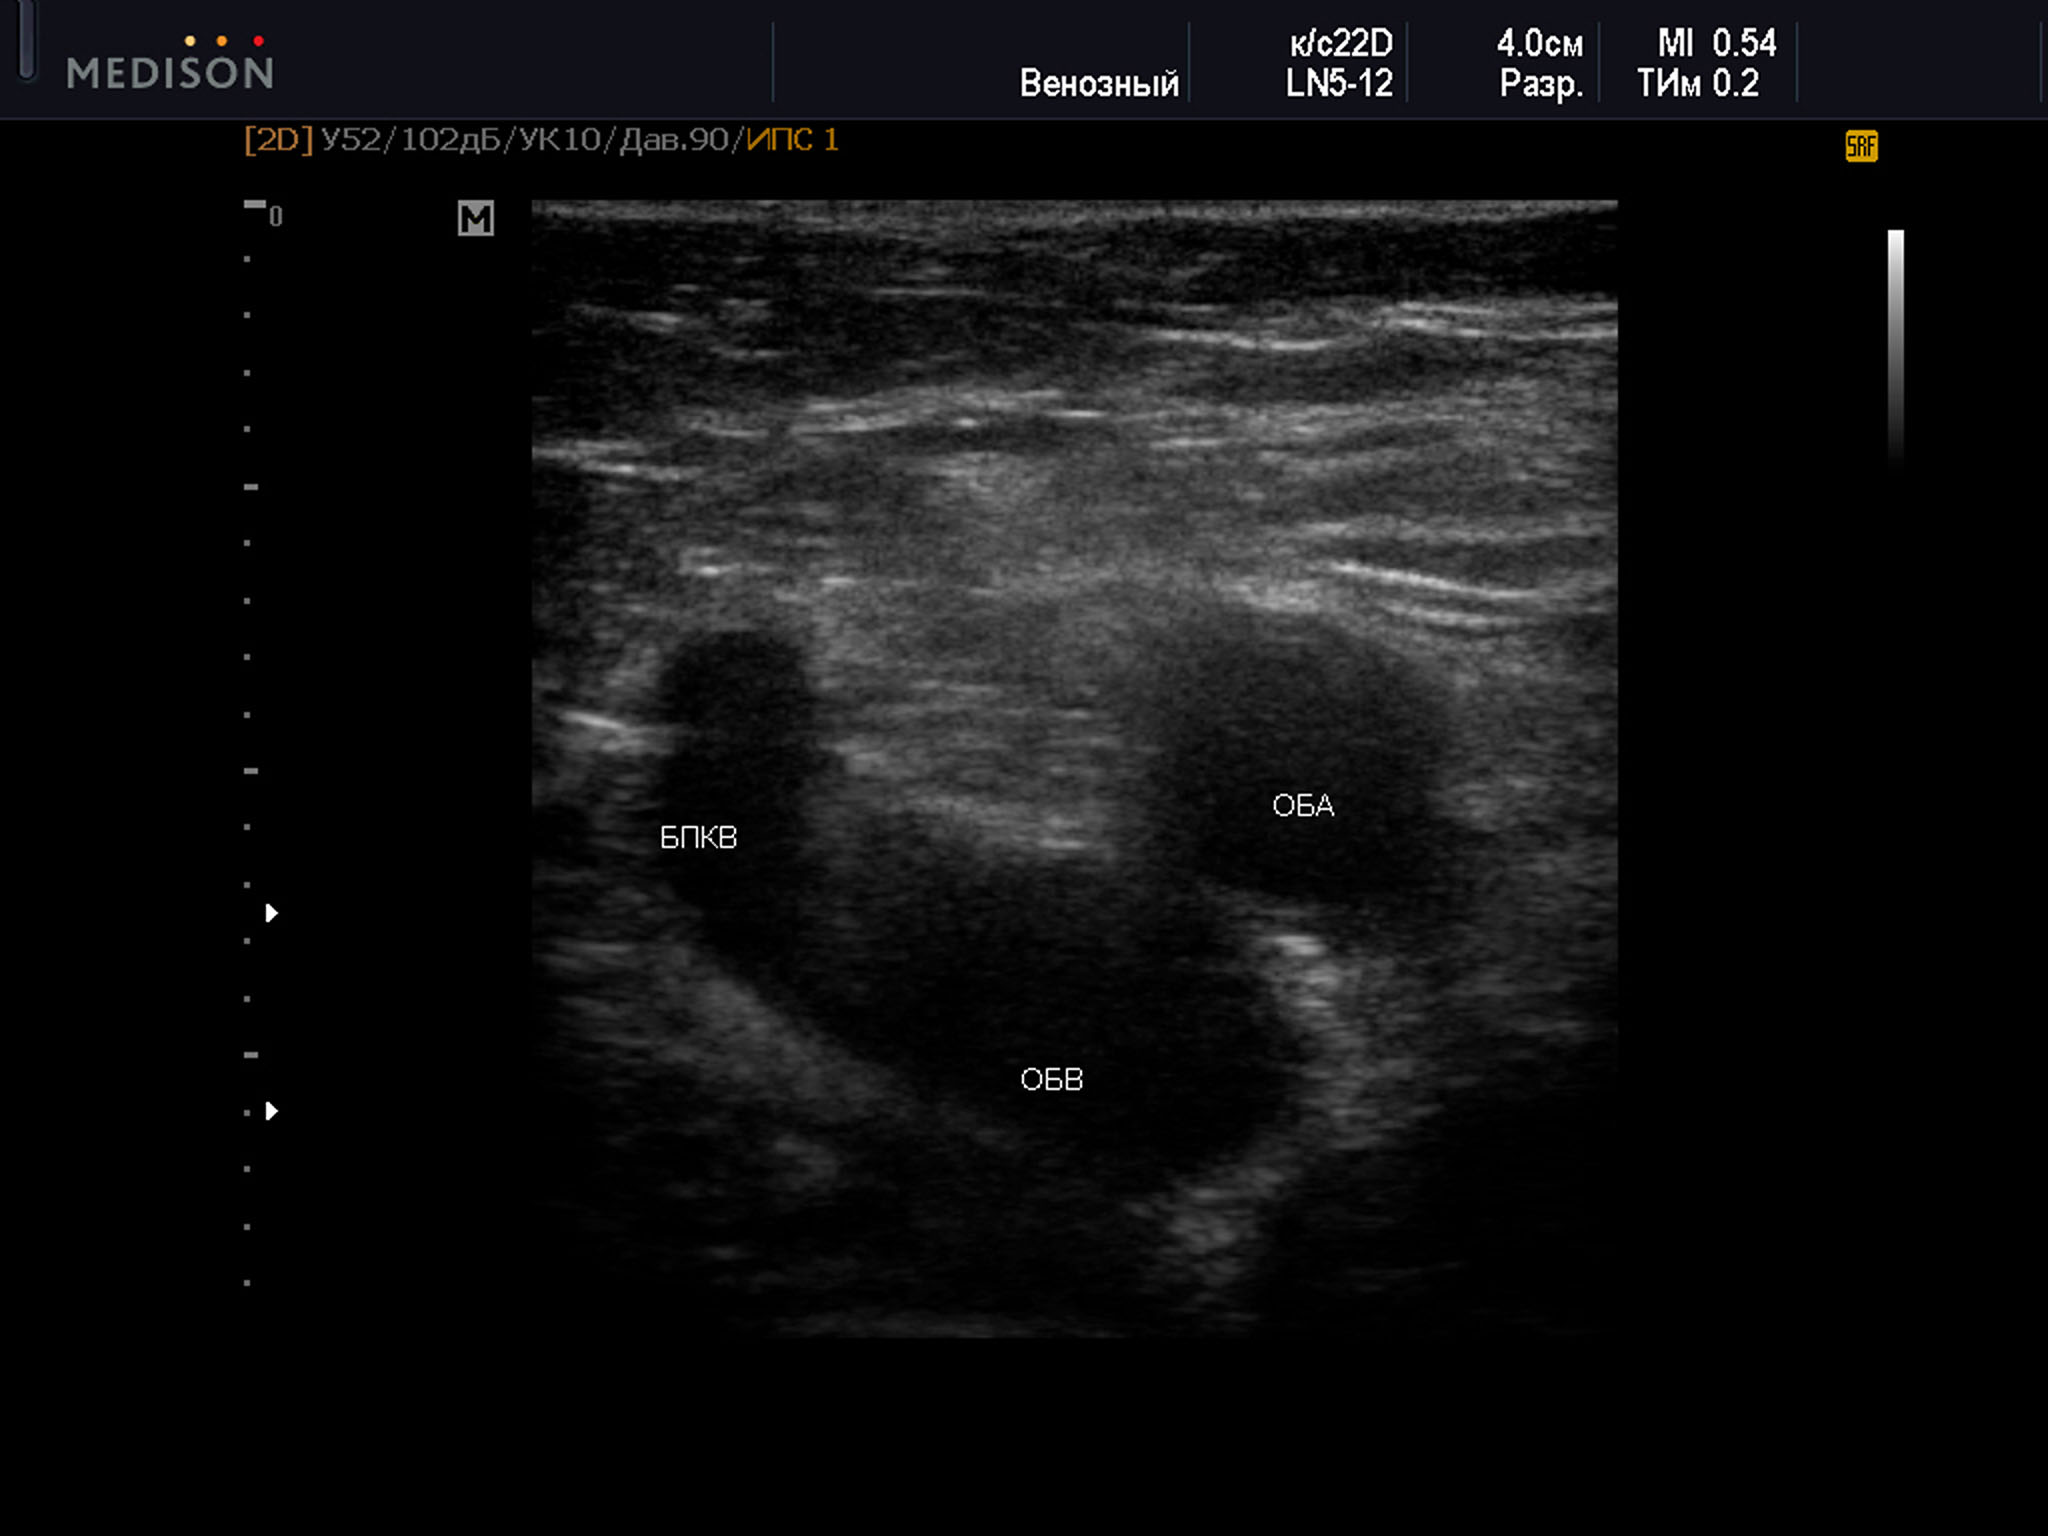

Пример диагностического ультразвукового изображения на уровне верхней трети бедра, поперечное сечение общей бедренной вены и общей бедренной артерии, Тип 3 взаимного положения сосудов

SonoAce R7, линейный датчик, женщина, 75 лет.

ОБА – общая бедренная артерия; ОБВ – общая бедренная вена; БПКВ – большая подкожная вена бедра

3 тип был выявлен среди 17% от общего числа участников наблюдения. Он встречался чаще, достигая 20,2% всех случаев, а справа в 14% наблюдений. У женщин этот тип диагностировался в 19,2%. В группе женщин слева данный вариант определялся в 25,4%, а справа только в 13,4% случаев. В группе мужчин он был выявлен в 13,6% всех наблюдений. Различия при этом оказались менее выраженными справа 14,9%, а слева — 12,2%. Возраст всех участников был с данным типом положения сосудов от 33 до 79 лет — 59,9±7,8 лет, среди женщин возраст был от 33 до 79 лет - 60,6 ± 7,0 лет, возраст мужчин был от 40 до 72 лет — 58,6 ± 9,0 лет.